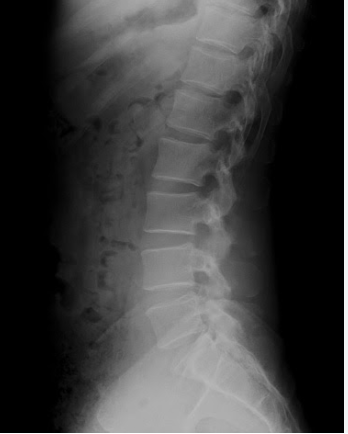

日本の医療教育は長い間、

骨に異常があるか

椎間板が潰れているか

神経が圧迫されているか

といった

画像で確認できる異常を見つける医学を中心に発展してきました。